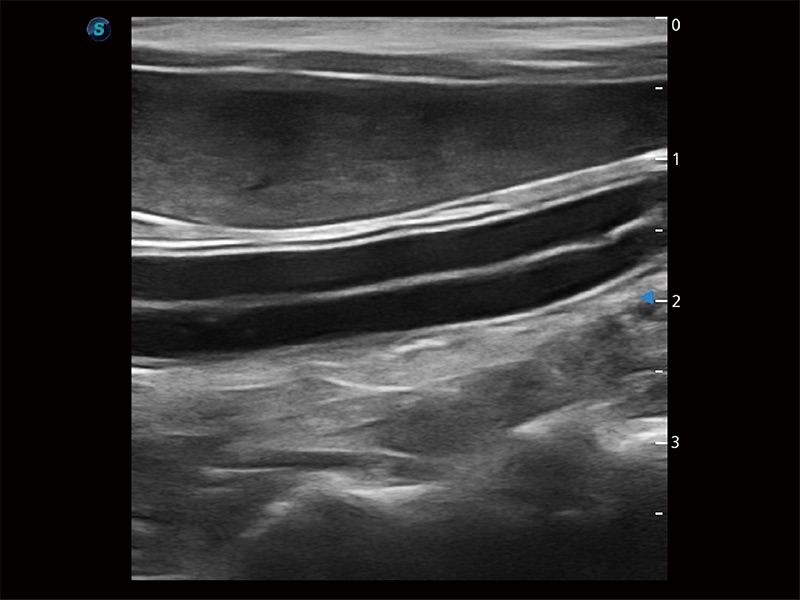

高性能和先進(jìn)的臨床應(yīng)用工具可以為動物醫(yī)生提供臨床信心。ProPet 80 搭載了先進(jìn)的腹部和淺表應(yīng)用工具,幫助醫(yī)生在日常臨床實(shí)踐中發(fā)揮前所未有的作用。

極大提升超低速微細(xì)血流的檢出能力,同時更精準(zhǔn)地濾除軟組織和超聲信號,為獸用醫(yī)生提供以往無法通過常規(guī)血流獲得的疾病診斷信息。

為精細(xì)結(jié)構(gòu)及組織邊緣提供高清晰度的圖像和更大的成像視野。幫助減輕醫(yī)生的用眼疲勞,快速精準(zhǔn)獲得測量的數(shù)據(jù)。